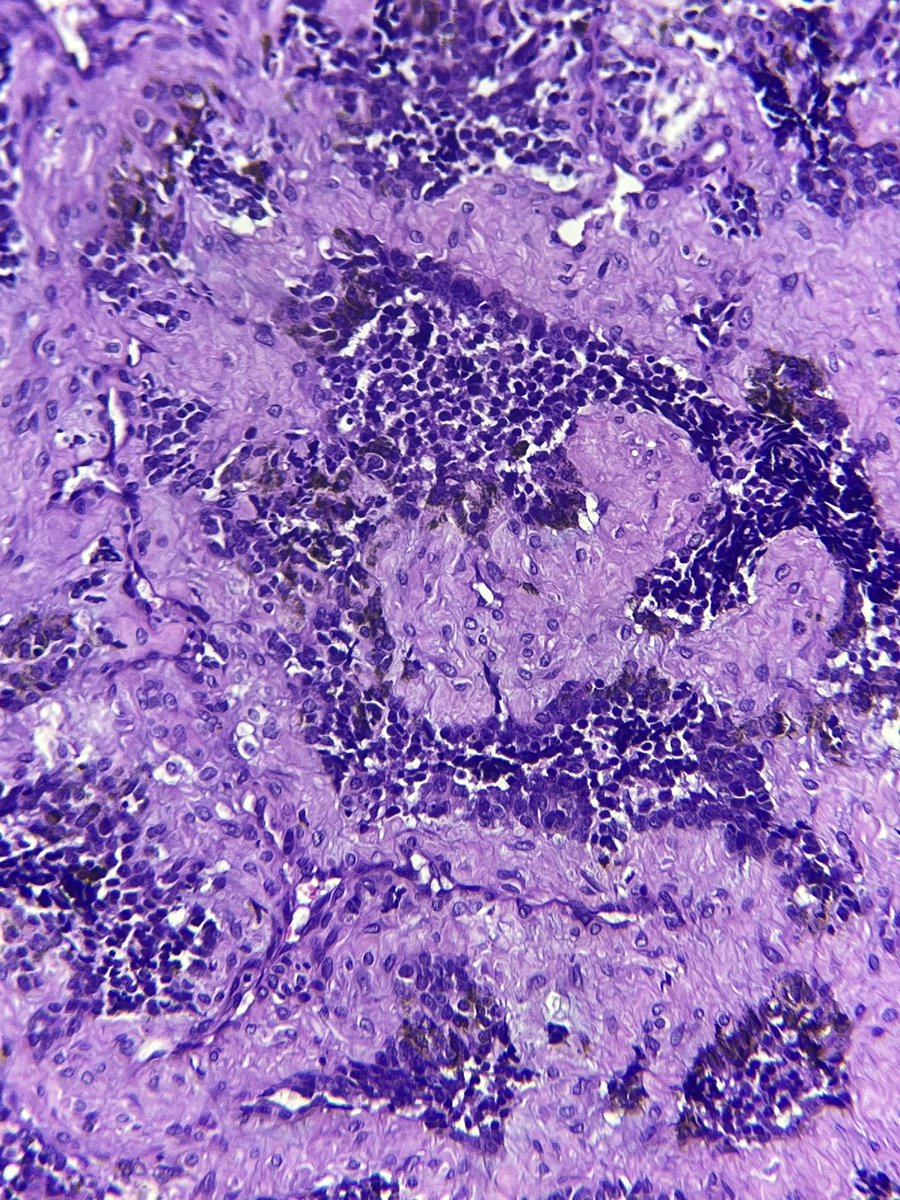

Oh me oh my 😱 what is happening in this gallbladder #GIpath